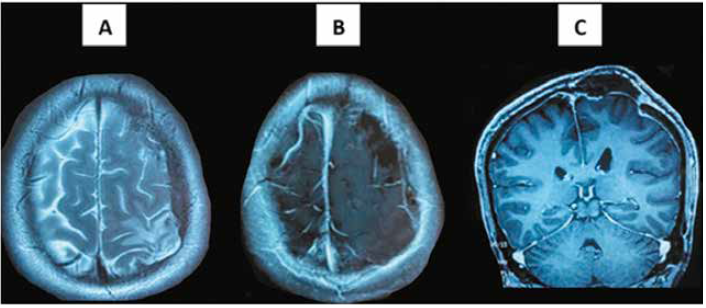

La resonancia magnética de cerebro con contraste a los 6 meses evidenció ausencia de recidiva de la lesión (Figura 3). El seguimiento postquirúrgico por neurocirugía, oncología, radiocirugía y hematología concluyó en la remisión de la lesión sin requerimiento de manejo médico adicional.

(A) T2 axial: área pequeña de encefalomalacia fronto-parietal izquierda, en relación con el área lesional antigua, con surcos cerebrales visibles. (B) T1C axial con contraste: no captación de contraste (gadolinio) en área donde se ubicó previamente la lesión. (C) T1C coronal con contraste: no captación de contraste a nivel fronto-parietal izquierdo; se evidencia ausencia de calota craneal en dicha área.